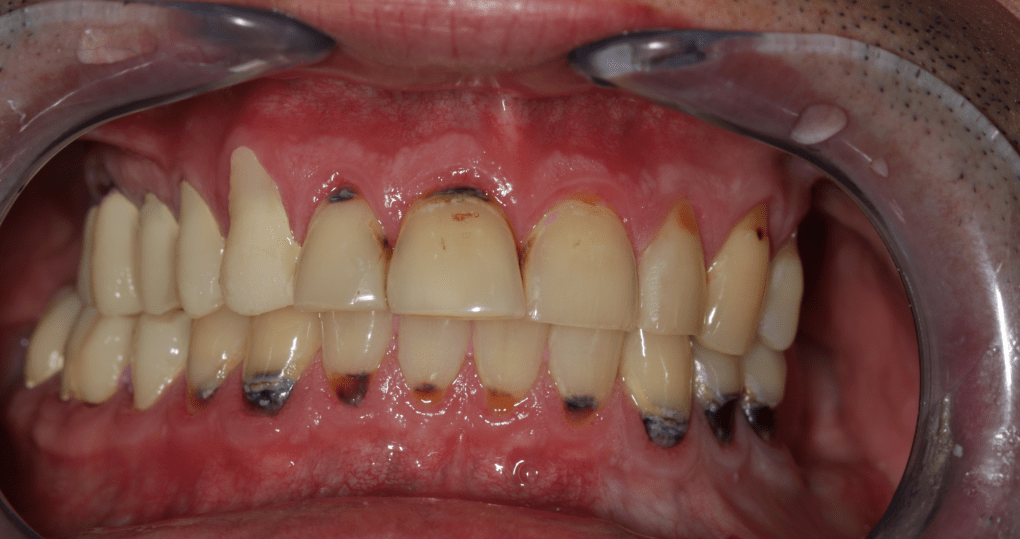

Páciensünk azért kereste fel fogászatunkat, mert évek óta állkapocsízületi problémákkal küzdött, melyek miatt fogai ápolását is elhanyagolta. Első találkozásunkkor szájnyitási nehézségekre, szimmetrikus állkapocsízületi kattogásra és éjszakai parafunkciós mozgásokra (csikorgatás, szorítás) panaszkodott, melyek megnehezítik mindennapjait.

Klinikai és radiológiai vizsgálatok alapján megállapítottam, hogy a túlterhelés (parafunkciók) jelei látszódnak a fogain is: abfrakciók – nyaki kopások és attríciók –, rágófelszíni kopások is kifejezettek voltak. Harapása igen bizonytalan tartományban mozgott, nem volt egy stabil helyzet, amelybe határozottan össze tudott volna zárni (csak kereste a megfelelő pozíciót.) TMI-vizsgálat során reciprok crepitációt (kattanás nyitáskor-záráskor is), myofascialis eltéréseket (hypertrófiás musculus masseter – túlterhelt rágóizom) és beszűkült mozgáspályákat találtam. Emellett sajnos a nem megfelelő szájhigiénés szokások miatt a fognyakak „sérült” részein szuvasodások is megjelentek, illetve a bal alsó hatos és a jobb felső hetes fog már oly mértékben destruálódott, hogy el kellett távolítani őket.

Ezek segítségével a fogtechnikai laboratórium elkészített egy hosszú távú, ideiglenes pótlást, amelyet a páciens 3 hónapon át hordott, természetesen szoros nyomon követés, kontrollok mellett. Ennyi idő alatt a páciens panaszai nagyrészt meg is oldódtak.

Miután a pácienssel megbizonyosodtunk a pótlás funkcionalitásának sikerességéről, készre kértük a fogtechnikai laborból azt a cirkóniumpótlást, amely a kisebb korrekciókon átesett ideiglenes pótlás tökéletesen pontos mása lett.

A páciens az elért eredménnyel mind funkcionálisan, mind esztétikailag azóta is maximálisan elégedett.